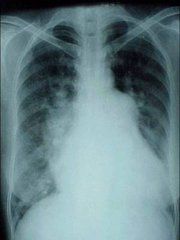

醫學影像學也稱醫學成像,醫學影像學MedicalImaging泛指通過X光成像(X-ray),電腦斷層掃描(CT),核磁共振成像(MRI),超聲成像(ultrasound),正子掃描(PET),腦電圖(EEG),腦磁圖(MEG),眼球追蹤(eye-tracking),穿顱磁波刺激(TMS)等現代成像技術檢查人體無法用非手術手段檢查的部位的過程。醫學成像又稱鹵化銀成像

醫學影象學主要包括X光成像儀器、CT(普通CT、螺鏇CT)、正子掃描(PET)、超聲(分B超、彩色都卜勒超聲、心臟彩超、三維彩超)、核磁共振成像(MRI)、心電圖儀器、腦電圖儀器等。

醫學影像學可以作為一種醫療輔助手段用於診斷和治療,也可以作為一種科研手段用於生命科學的研究中。診斷主要包括(透視、放射線片、CT、MRI、超聲、數字減影、血管造影)。